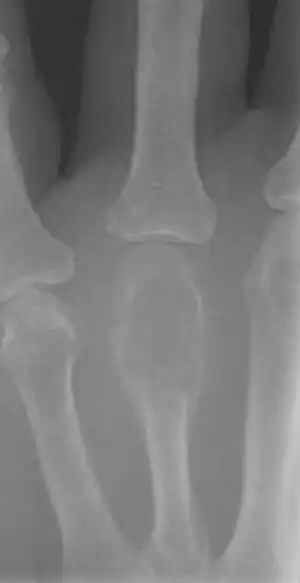

Imaging

On X-ray, giant-cell tumors (GCTs) are lytic/lucent lesions that have an epiphyseal location and grow to the articular surface of the involved bone.[11] Radiologically the tumors may show characteristic 'soap bubble' appearance.[12] They are distinguishable from other bony tumors in that GCTs usually have a nonsclerotic and sharply defined border. About 5% of giant-cell tumors metastasize, usually to a lung, which may be benign metastasis,[13] when the diagnosis of giant-cell tumor is suspected, a chest X-ray or computed tomography may be needed. MRI can be used to assess intramedullary and soft tissue extension.